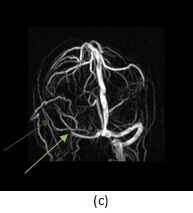

Figure 1: (a, red arrow) T2 and T1 (b,blue arrow) images demonstrate increased signal in the right sigmoid sinus. This finding could be due to either thrombosis or slow venous flow. There is also fluid in the mastoid air cells (purple arrow)- while fluid in the mastoid air cells is typically sterile, fluid can reflect infection in the case of mastoiditis, and mastoiditis predisposes to venous thrombosis.(c,green arrow) 3-D reconstructions from an MR venogram demonstrate abrupt cut off of contrast in the right transverse sinus with the suggestion of collateral flow (brown arrow) more consistent with thrombosis.

If there is clinical or imaging suspicion for venous sinus thrombosis, a CT venogram or MR venogram should be performed. These studies provide better delineation of the sinuses and are typically performed with contrast. A common pitfall in the diagnosis is dural sinus thrombosis is the hypoplastic transverse sinus which can mimic occlusion. Thrombosis typically causes a frayed appearance to the venous sinus that may be associated with collaterals.

Large arachnoid granulations can also appear as filling defects within the sinus however, arachnoid granulations tend to be ovoid in shape while thrombosis tends to be long and linear. Arachnoid granulation should also have CSF signal intensity on MR and CT